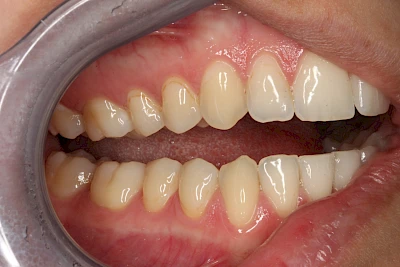

Verfärbungen an Zähnen können außen aufgelagert oder im Zahn eingelagert sein.

Von außen (exogen) eher dunkel gefärbt und meist mehrere Zähne betroffen:

Von innen (endogen)